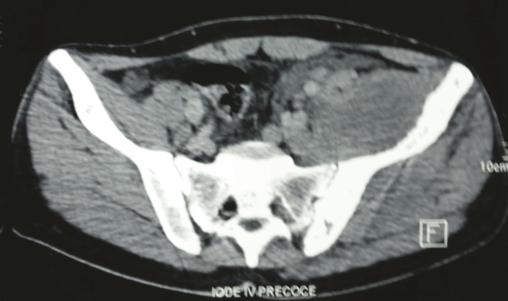

Les radiographies standards mettent en évidence une vertèbre ivoire L1 ainsi qu’une ostéocondensation de l’os iliaque gauche (fig. 1 ). Le scanner thoraco-abdomino-pelvien montre une atteinte osseuse mixte de l’aile iliaque gauche (fig. 2 ), un envahissement des parties molles (avec augmentation des volumes des muscles fessiers et du psoas [fig. 3 ] expliquant la sciatalgie), une néphromégalie unilatérale, une splénomégalie nodulaire et de multiples adénopathies abdomino-pelviennes et thoraciques.

La tomodensitométrie (TDM), quant à elle, permet de déterminer le stade et l’extension du lymphome et d’assurer le suivi des patients. L’imagerie par résonance magnétique (IRM) est un examen très sensible pour l’étude de l’envahissement des parties molles et celle de l’extension dans la moelle osseuse. L’infiltration lymphomateuse apparaît en hyposignal ou sous forme de signal hétérogène en T1 et en hypersignal T2 avec prise de contraste après injection de gadolinium.